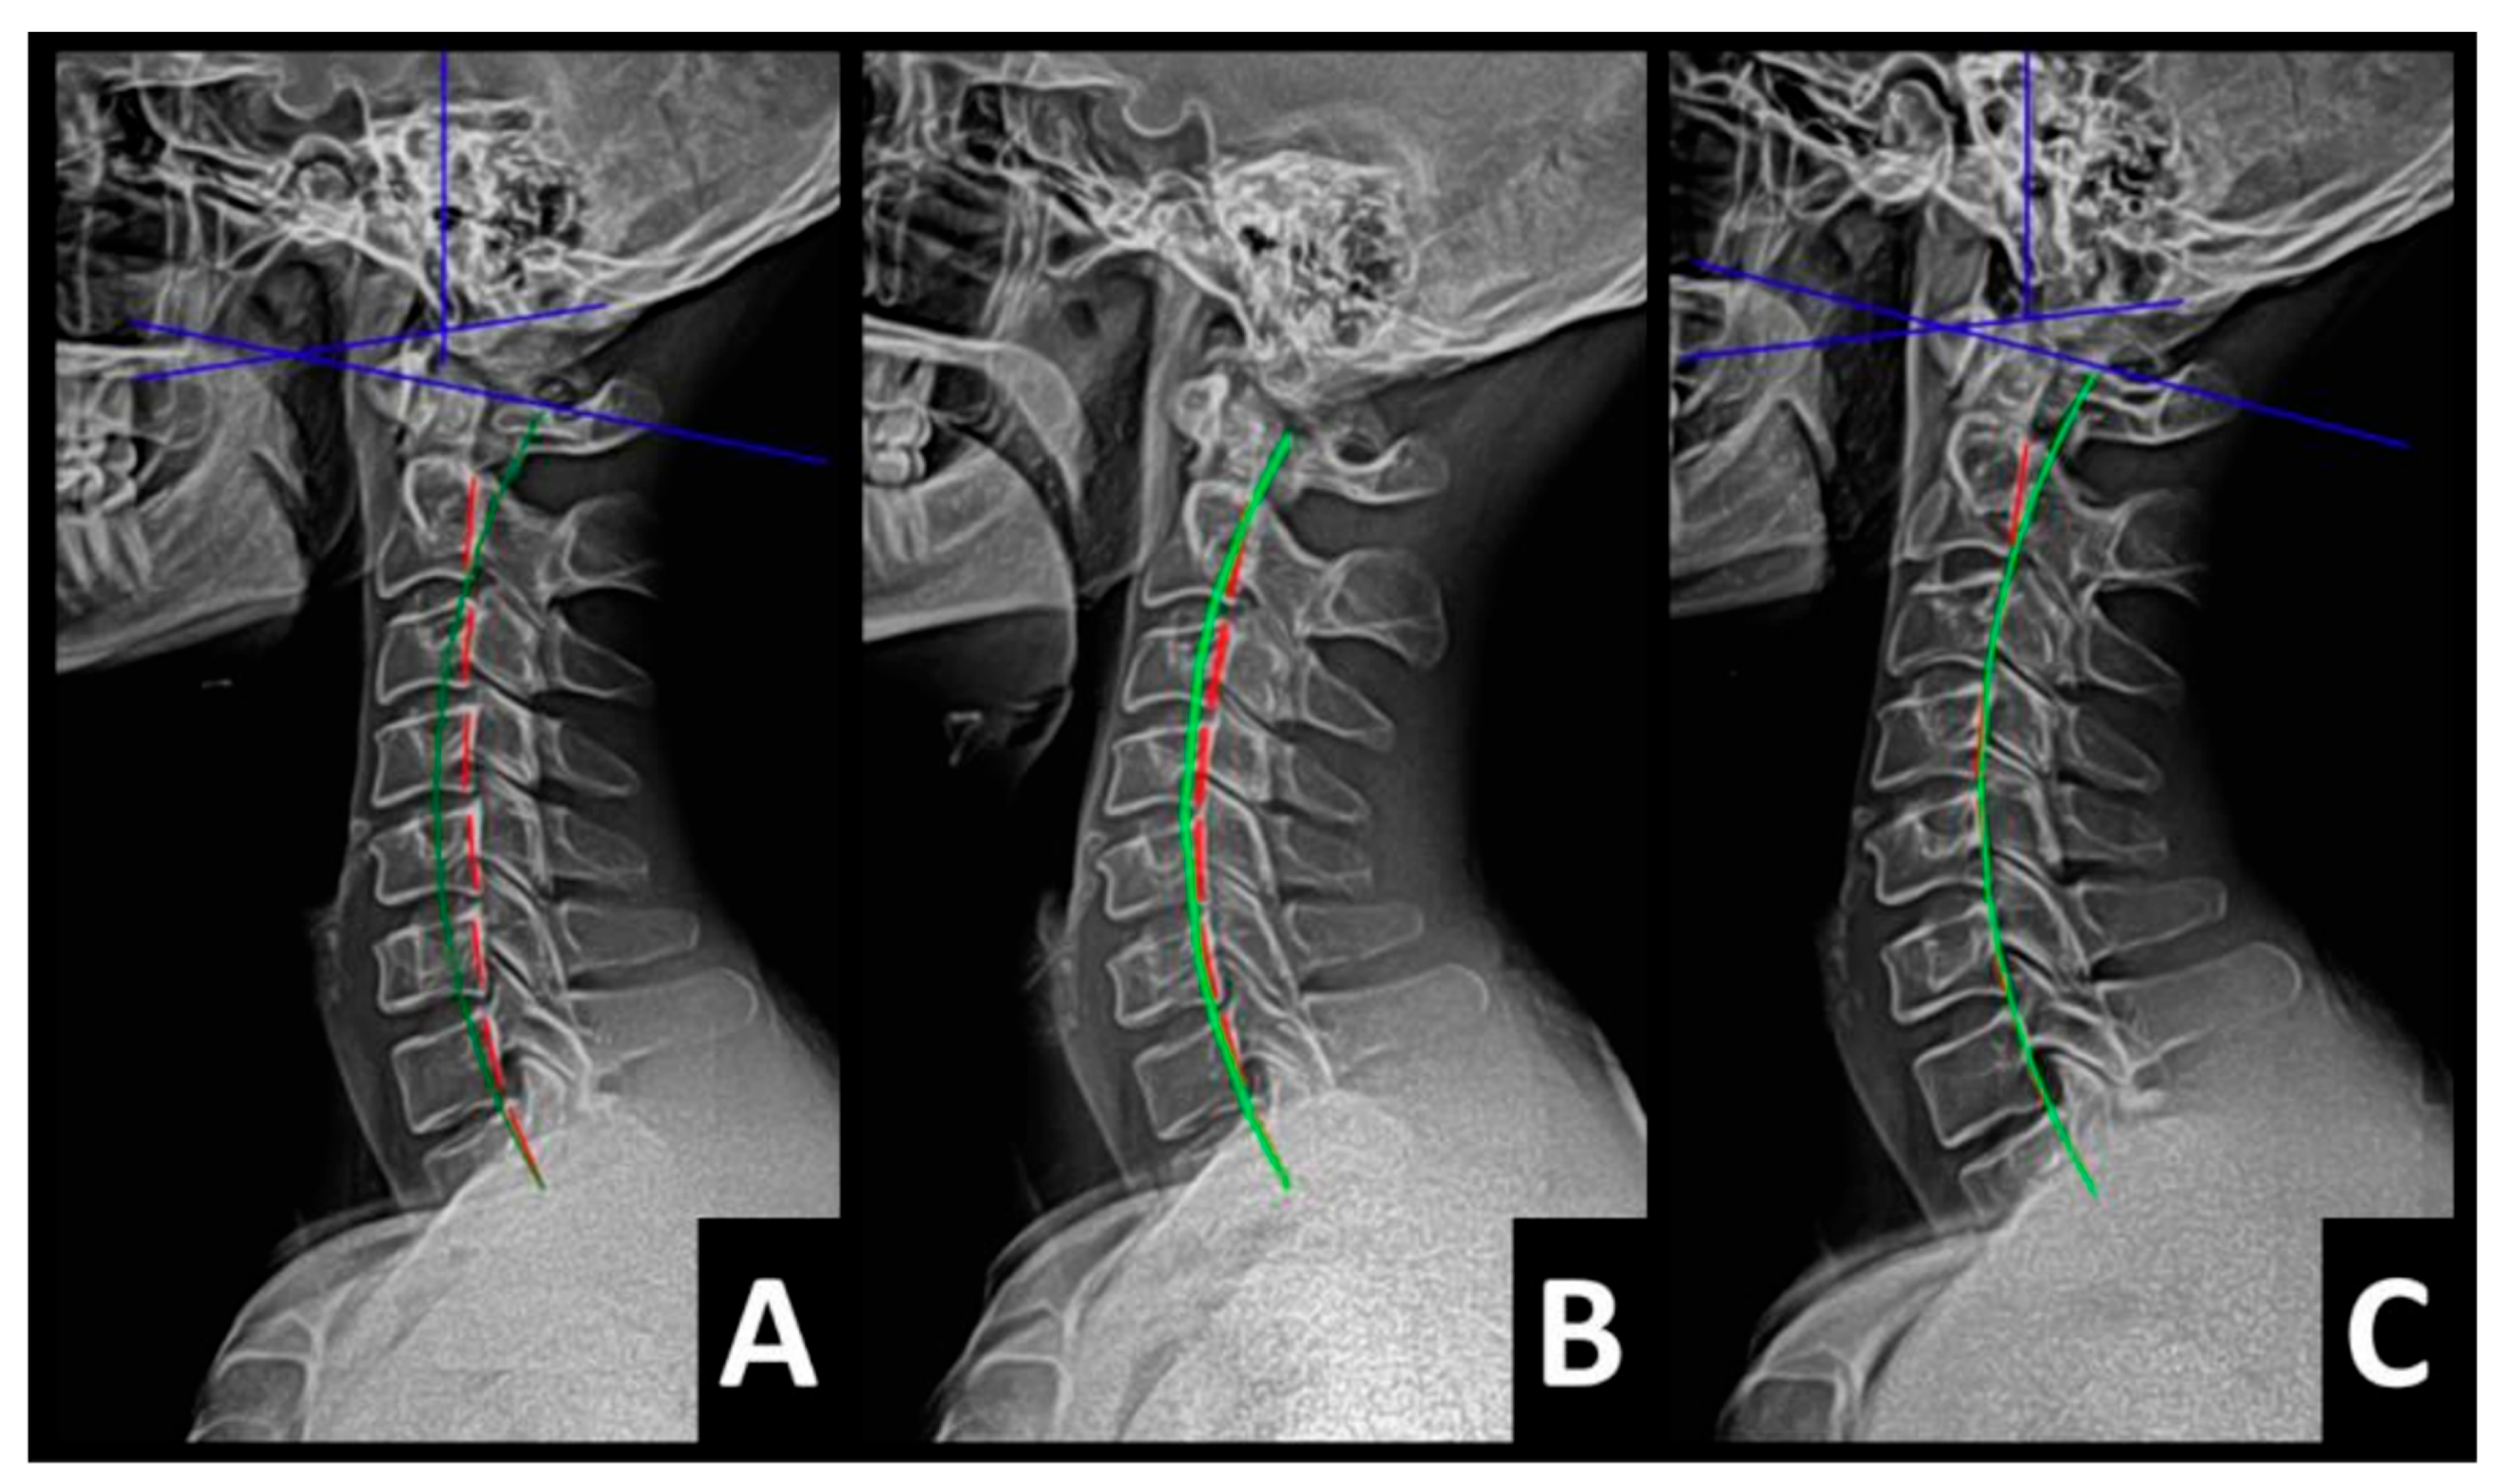

Radiography of the spine was performed with the patient upright in neutral position. Anterior–posterior (AP) and lateral films were assessed using PostureRay® digital radiographic mensuration software (Posture Co, Inc., Trinity, FL, USA) [14]. The program uses the Risser–Ferguson measurement for the AP views and the Harrison posterior tangent method (HPTM) of measurement for the lateral views. The program also compares the patient alignment of both segmental and global measurements to models of ideal spine parameters; prior studies have shown exceptionally high reliability using this system [15]. The sagittal spine absolute rotation angle (ARA) from the 2nd cervical vertebra to the 7th (ARAC2–C7) measured −18.1° (average is −34°, ideal is −42°, pain threshold is −20° [16]) (Figure 2, Figure 3, Figure 4 and Figure 5) and the AP cervical X-ray demonstrated a right lateral flexion angle relative to true vertical of the lower cervical and upper thoracic spine (cervicodorsal angle (CDA)) measuring 5.6° (ideal is 0° [16]) with a right translation of C2 with respect to T5 (TXC2–T5) measuring −17.2 mm (ideal is 0 mm). There was an increased mid-thoracic angle with a right-sided concavity from T1 to T12 (MTAT1–T12) of 9.1° (ideal is 0° [16]) with an increased translation at T8 apex of mid-thoracic angle with respect to T12 (+TXT8–T12) measuring 15.2 mm (ideal is 0 mm). There was a decreased sagittal curvature of the lumbar spine from L1 to L5 (ARAL1–L5) measuring −17.9° (ideal is −40°, average range is 35–45° [16]). The modified Ferguson pelvic radiograph demonstrated a sacral base unleveling in the frontal plane measuring −11.3 mm, being lower on the right. There was a lumbosacral angle from L1 to L5 with an L3 apex (LSA L1–L5) of −84.9° (ideal is 90°).

Post-treatment posture analysis showed improved posture (Figure 1A–C). Post-treatment radiographic examination revealed the following: improved ARAC2–C7 measuring −29.4° (vs. −18.1°); rotation around the z-axis of the thorax (RZT5) measured 1.8° (vs. normal 0°); improved -TxC2–T5 measuring −5.7 mm (vs. −17.2 mm); improved MTA T1–T12 measuring 2.1° (vs. 9.1°); improved +TxT8–T12 measuring 3.5 mm (vs. 15.2 mm); improved ARAL1–L5 measuring −25.1° (vs. −17.9°); improved sacral base unleveling in the frontal plane measuring −1.0 mm low on the left (vs. −11.3 mm low on the right); and improved LSA L1–L5 of −88.0° (vs. −84.9°) (Figure 2B, Figure 3B, Figure 4B and Figure 5B). Post-treatment RODI score was 12% (vs. 54%), indicating minimal disability. All post-treatment SF-36 scores showed improvements (Table 1). One-year follow-up posture analysis showed a maintenance of the improved posture. One-year follow-up radiographic examination revealed maintained sagittal balance and coronal spinal alignment correction improvements (Figure 2C, Figure 3C, Figure 4C and Figure 5C). One-year follow-up RODI score was 2% indicating minimal or resolved disability from baseline (54%). Post-treatment SF-36 scores showed maintained or further improved HRQoL measures reported by the patient. Long term follow-up found minimal forward head posture on the lateral posture photograph, a slight return to baseline on the A-P cervical radiograph with a right head translation measuring 7 mm. Lateral cervical radiograph assessment at long-term found the lordosis to be well maintained at 34° ARA with minimal C2-vertical anterior head translation of 6 mm. lateral lumbar radiograph showed a slight loss of lordosis at follow-up of 19°. All subjective initial symptoms were reported to be resolved at long-term follow-up. Long term follow-up SF-36 scores were the same as post-treatment with the exception of vitality, which was slightly improved (Table 1). There were no positive orthopedic or neurological tests at follow-up. The patient continued to use the ProLordotic neck exerciser at home 1–3 times per week for up to 10 min (Figure 7).

Figure 2. (AC) Pre-treatment, post-treatment, and 1-year follow-up neutral lateral cervical radiographs. Image Features: The green line represents a normal, ideal sagittal cervical spinal alignment. The red line represents the actual posterior tangent lines of the C2–1 vertebrae.